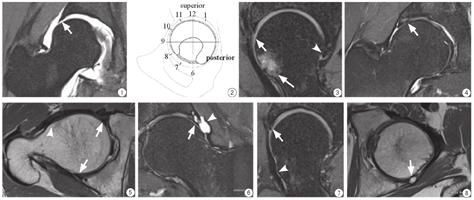

4 髋臼盂唇的正常MRI表现正常髋臼盂唇在MR图像上一般为三角形,呈均匀低信号,边缘光滑,盂唇旁隐窝显示清晰(图1)。

右髋关节直接MR关节造影(d-MRA)冠状面图像,可见正常三角形的外上盂唇(白箭)

图3

髋关节斜矢状PDWI-FS图像,可以显示前盂唇(白箭)及后盂唇(箭头),前盂唇可见撕裂,后盂唇正常,股骨头颈交界部可见骨髓水肿(白长箭)

图4

右髋关节冠状PDWI-FS图像,可以显示外上盂唇撕裂(白箭)

图5

髋关节横断位PDWI图像,除了可以显示髋臼盂唇(白箭)之外,还可以显示髋臼及股骨近端骨质情况,本病例股骨头颈交接部出现骨性突起(箭头),诊断为凸轮型撞击综合征

图6

髋关节冠状面PDWI-FS图像,显示髋臼外上盂唇撕裂(白箭),伴盂唇旁囊肿形成(箭头)

图7

髋关节斜矢状面PDWI-FS图像,显示髋臼前盂唇撕裂(白箭),伴股骨头颈交界处骨性突起(箭头),诊断为凸轮型撞击综合征

图8

髋关节横断面PDWI图像,显示髋臼后盂唇撕裂(白箭)

5 髋臼盂唇MRI读片方法将髋臼缘按照时钟图分为12个钟点,前盂唇、外上盂唇及后盂唇按照顺时针方向依次分布于8点至5点的位置,5点至8点的位置由髋臼横韧带覆盖,表面无盂唇覆盖[6] (图2)。

(1)斜矢状面图像:主要用于观察前盂唇及后盂唇,即8点至11点方向和3点至5点方向(图3)。(2)冠状面图像:主要观察外上盂唇,即11点到3点方向(图4)。(3)横断面图像:是对斜矢状面和冠状面图像的补充(图5);在横断面质子加权像中可以将高信号的骨髓和低信号的盂唇清晰分开,可以观察髋臼及股骨近端骨质情况,有助于判断有无骨质增生、髋臼过度覆盖或髋臼发育不良等。

6 髋臼盂唇损伤的MR诊断标准(1)MRI诊断标准:按照2005年Douglus等提出的诊断标准,正常盂唇为附着于髋臼缘的均匀三角形低信号,盂唇撕裂表现为盂唇实质内高信号累及关节面或关节囊面,盂唇退变表现为盂唇内局限性稍高信号,未达关节面或关节囊面[7]。(2)d-MRA诊断标准:按照Czerny提出的诊断标准,正常盂唇为附着于髋臼缘的均匀三角形低信号,Ⅰ期为盂唇内高信号未达关节面或关节囊面,Ⅱ期为盂唇内高信号达关节面,Ⅲ期为盂唇与髋臼缘分离[8]。

7 髋臼盂唇撕裂的表现及常见位置髋臼盂唇发生撕裂时,液体或者滑膜会进入撕裂的盂唇内,在MR图像上表现为低信号的盂唇内出现高信号。盂唇撕裂常见于髋臼前盂唇上部及外上盂唇前部,后盂唇撕裂较为少见(图6,图7,图8,图9,图10)。